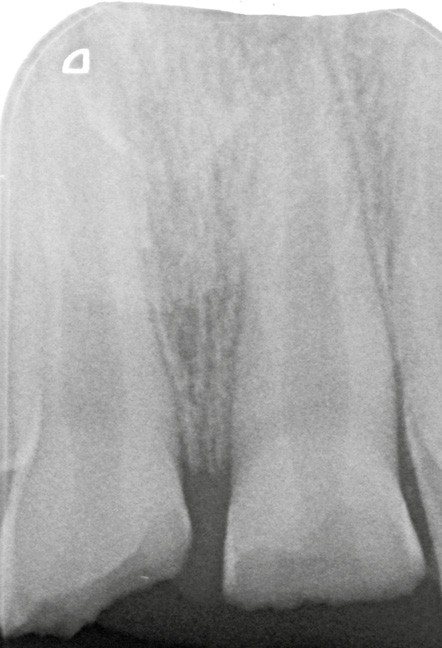

L’examen radiologique montre que les racines de 11 et 21 ne sont pas totalement édifiées (fig. 3). La priorité sera alors de conserver la vitalité pulpaire de ces dents immatures.